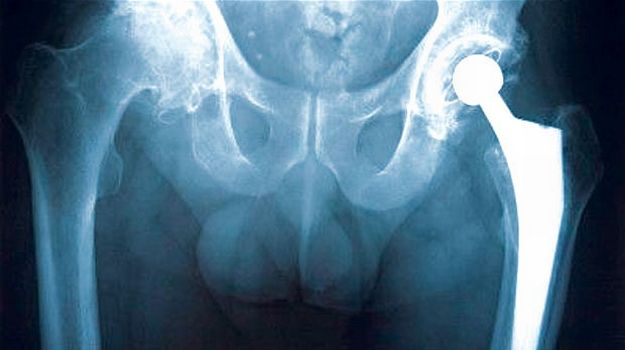

Desetine hiljada pacijenata u Velikoj Britaniji možda se truju umjetnim kukovima. Trideset hiljada ljudi u Velikoj Britaniji ima ugrađene umjetne metalne kukove. Problem s metalnim kukovima nastaje u zglobu implantanta koji se troši trljanjem dviju pločica

kuk-snimakMetal može ući u krvotok te izazvati upale koje mogu uništiti mišiće i kosti. Zbog toga su britanske medicinske službe krenule u sastavljanje novih medicinskih standarda i pravila za ugradnju metalnih kukova. Britanska agencija za sigurnost medicinskih proizvoda (Medicines and Healthcare products Regulatory Agency, MHRA) smatra da "metalni mogu izazvati sistemsko trovanje ljudskog organizma".